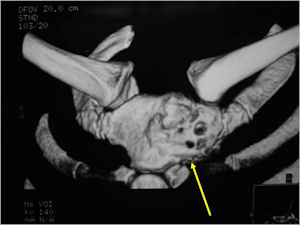

CT Scan:

- More useful for detecting mineralization and evaluating extent of bone destruction than plain X-ray

MRI:

- Also useful in determining extent